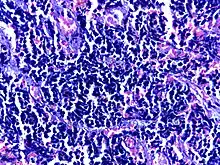

![]() | Small cell carcinoma of lung | Micograph of small Cell Carcinoma Lung. The tumor appears blue because the malignant epithelial cells are small with scanty cytoplasm, nuclei shows finely granulated chromatin. Cells are seen in clusters. There is nuclear overlapping with moulding and crushing. | Category: Histopathology of small cell lung cancer | Small cell lung cancer |